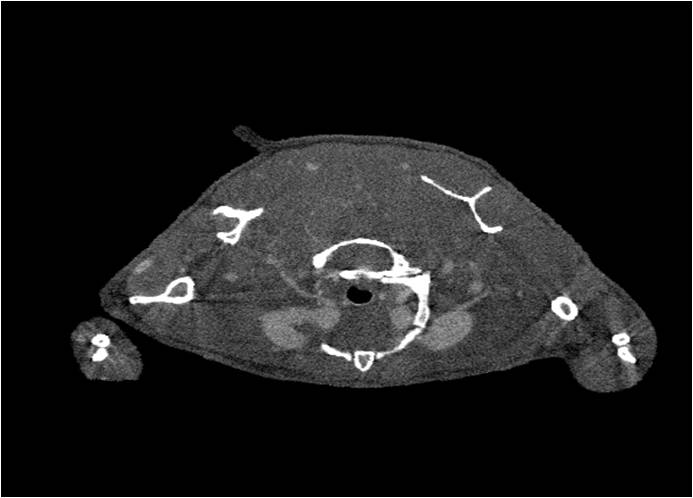

胸部和心血管的層析成像 胸部和心血管的3D圖像